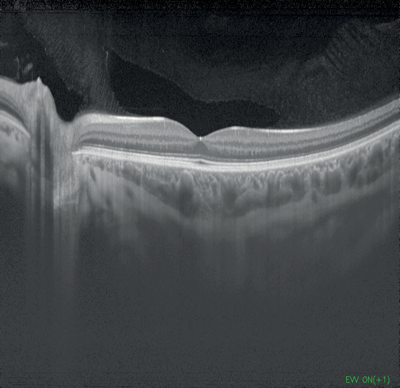

Figures 1-4: Swept-source OCT (DRI OCT-1 Triton, Topcon) images of healthy eyes that clearly delineate features in the vitreous, including area of Martegiani, bursa premacularis and posterior hyaloid, right through to the sclera, in the same single scan.

Topcon’s newly-introduced swept-source DRI OCT Triton can capture 256 B-scans in less than three seconds, with high speed scanning of 100,000 A-scans per second and a 1050nm wavelength which can penetrate easily through cataracts and haemorrhages. It features widefield 12 by 9mm scan screens for both glaucoma and macular pathology in one scan, with consistent signal strength from cortical vitreous to the sclera with an average of up to 128 times, automatic detection of seven retinal layers, as well as 2.6 micron digital resolution. The DRI OCT Triton has a built-in high resolution colour fundus camera, fundus guided acquisition (SmarTrack) and the option of an anterior imaging module. The Triton Plus also features fundus autofluorescence and fluorescein angiography, and an OCT angiography module is currently under development.